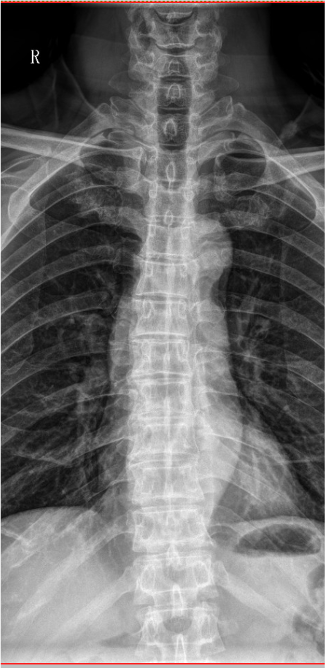

【影像】胸椎正侧位X线片见胸椎退行性变,胸椎轻度侧弯。